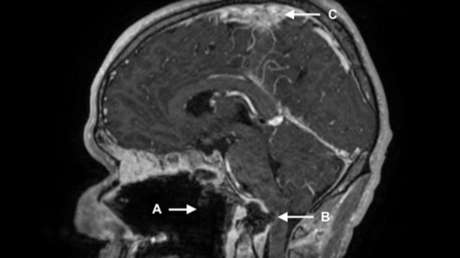

A pesar de esto, el hombre volvió a emergencias cuatro meses más tarde con una sospecha de sobredosis de estupefacientes. Presentaba una condición potencialmente mortal dado que padecía una lesión cerebral y severos daños en la médula espinal. Exámenes médicos revelaron además presencia de líquido e hinchazón de tejidos blandos en el área donde se conectan el cráneo y la columna. El paciente fue tratado nuevamente con antibióticos; sin embargo, falleció poco después.